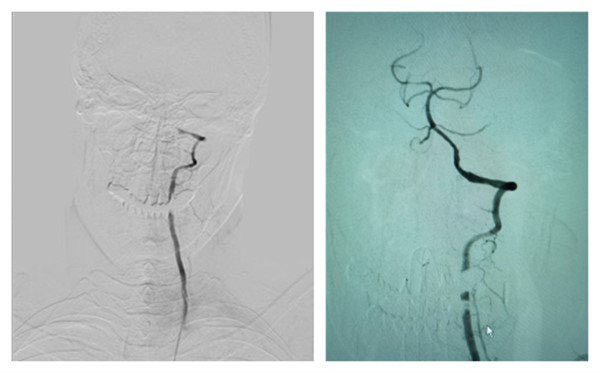

近期我院神经内科收治了一名椎基底动脉系统多发脑梗死患者,患者积极药物治疗后半年内仍反复发生3次椎基底动脉系统脑梗死,当地医院行磁共振血管成像示双侧椎动脉及基底动脉闭塞。患者家属听闻我院张桂莲教授团队行颅内大血管非急性期再通治疗经验丰富,再通率高,手术并发症低,专程从山西慕名前来就医。入院时患者卧床,无法坐起及站立,入院后行脑血管造影示右侧椎动脉V1段以远闭塞,左侧椎动脉V3段以远闭塞,基底动脉通过双侧颈内动脉系统逆行显影,闭塞段直线距离长达4.5厘米。

术前(左)与术后(右)颅内血管

张桂莲教授及团队对患者进行临床症状、高分辨磁共振及CT灌注成像等影像学检查、推测闭塞时间、甄别原始闭塞点、预判围手术期风险及远期再闭塞率等多方面评估,同时详细向患者及家属讲明再通治疗的必要性和可能出现的风险后,为患者进行了椎基底动脉闭塞再通治疗,术中导丝顺利通过闭塞段、球囊扩张后植入2枚支架,血管成功再通。术后入住神经内科重症监护室,密切监测患者血压/脑血流及神经系统情况变化,患者无围手术期并发症发生,术后1周患者经人搀扶可行走,复查头颅CTA示椎基底动脉系统显影良好。